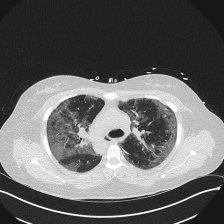

On the other hand, the visualized masks of the comparison methods for the binary and multi-classes Covid-19 infection segmentation are: Unet++ Zhou et al. (2018), CopleNet Wang et al. (2020), MISSFormer Huang et al. (2022) and UCTransUnet Wang et al. (2022a), and for multi-classes segmentation task are Att-Unet Oktay et al. (2018), SCOATNet Zhao et al. (2021), MISSFormer Huang et al. (2022) and UCTransUnet Wang et al. (2022a), which showed a competitive performance with our proposed approach (see Section 5.4).

The four visualized examples in Figure 6 are from the binary segmentation experiments of Dataset_2. The first example shows a case in which infection has spread to both lungs and appears as a GGO and small consolidation region at the bottom of the right lung. The comparison between the Unet++ mask and the ground truth (GT) shows that the Unet++ architecture fails in segmenting most of the infection regions. The CopleNet, MISSFormer and UCTransNet masks show improved segmentation performance compared to Unet++. However, these architectures still miss some infected regions or segment lung tissues as infection instead. The mask of our proposed approach shows high similarity with GT in term of the number of regions and their global shape. Both examples 2 and 3 are cases where the infection has a peripheral distribution. The visualized masks show that the proposed D-TrAttUnet is the best architecture consistent with the ground truth. The fourth example depicts a severe case where the infection has spread to most of the lung regions. The visualized masks exhibit that our proposed architecture performs better than the comparison architectures.

Slice Unet++ CopleNet MISSFormer UCTransNet D-TrAttUnet GT

Figure 6: Visual comparison of a segmentation model trained with different segmentation architectures for Binary Covid-19 segmentation using Dataset_2 and Dataset_3.